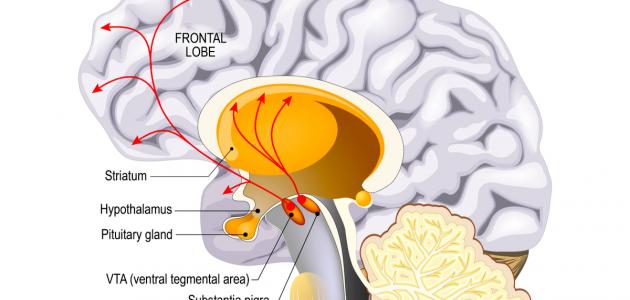

4.دوبامين مشان النادي والعضلات او مشان يوقف الشيخوخة او يجدد الخلايا ماراح يفيدهم تعرف ليش ؟

لان الحاجز لا يسمح للدوبامين بالدخول الى الدماغ لذالك مهما اخذت دوبامين من الخارج لن تستفيد شي لكن هذا الحاجز يسمح بدخول الموكونا او ال دوبا وعند وصولها يتم تحويلها الى دوبامين وبنفس

لان الحاجز لا يسمح للدوبامين بالدخول الى الدماغ لذالك مهما اخذت دوبامين من الخارج لن تستفيد شي لكن هذا الحاجز يسمح بدخول الموكونا او ال دوبا وعند وصولها يتم تحويلها الى دوبامين وبنفس